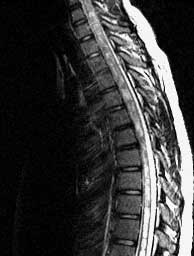

FSE T2 sagittals

Septated cavity with CSF signal extending form C3 to the conus. Peglike cerebellar tonsils herniated well below the foramen magnum.